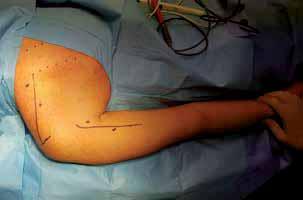

RYCINA 86.2.

Obraz kliniczny stopy po złamaniu kości piętowej (pęcherz jako objaw martwicy kolejnych warstw tkanki skórnej, patognomiczny objaw Mondora od strony podeszwowej śródstopia).